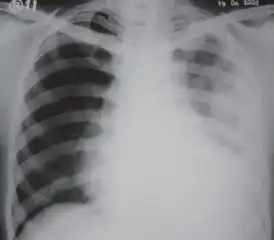

CXR of an individual affected by fibrothorax (consequence of tuberculosis) -

Extensive left-sided fibrothorax -

Chest radiograph displaying inhomogeneous opacification of the left half of the chest that is fibrothorax -

A fibrothorax can typically be diagnosed by taking an appropriate medical history in combination with the use of appropriate imaging techniques such as a plain chest X-ray or CT scan.[1] These imaging techniques can detect fibrothorax and pleural thickening that surround the lungs.[11] The presence of a thickened peel with or without calcification are common features of fibrothorax when imaged.[1] CT scans can more readily differentiate whether pleural thickening is due to extra fat deposition or true pleural thickening than X-rays.[1]

If a fibrothorax is severe, the thickening may restrict the lung on the affected side causing a loss of lung volume.[11] Additionally, the mediastinum may be physically shifted toward the affected side.[1] A reduction in the size of one side of the chest (hemithorax) on an X-ray or CT scan of the chest suggests chronic scarring.[9] Signs of the underlying disease causing the fibrothorax are also occasionally seen on the X-ray.[9] A CT scan may show features similar to those seen on a plain X-ray.[11] Lung function testing typically demonstrates findings consistent with restrictive lung disease.[9]